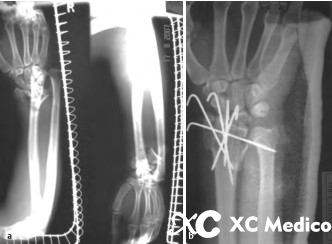

13. Используйте внешние фиксаторы для обработки обожженных переломов дистального радиуса. Внешние фиксаторы подходят для тяжелых переломов дистального радиуса, сопровождаемого огромным отеком, открытыми переломами или местными кожными условиями, которые не позволяют внутреннюю фиксацию (например, фиксацию пластин) (рисунки AD ниже).